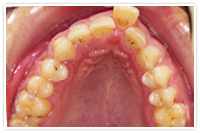

上顎の前歯一本が出ているのと、下顎の前歯の乱杭歯を部分矯正で治した症例

- 上顎の前歯一本が出ているのと、下顎の前歯の乱杭歯が気になるとのことでご来院されました。

- 上顎10本、下顎6本の歯の裏側に装置を接着し、歯と歯の間を少しずつ削合(ディスキング)して、出っ歯にならないように配慮しながら整列しました。約4ヶ月で上下共に保定に移行しました。